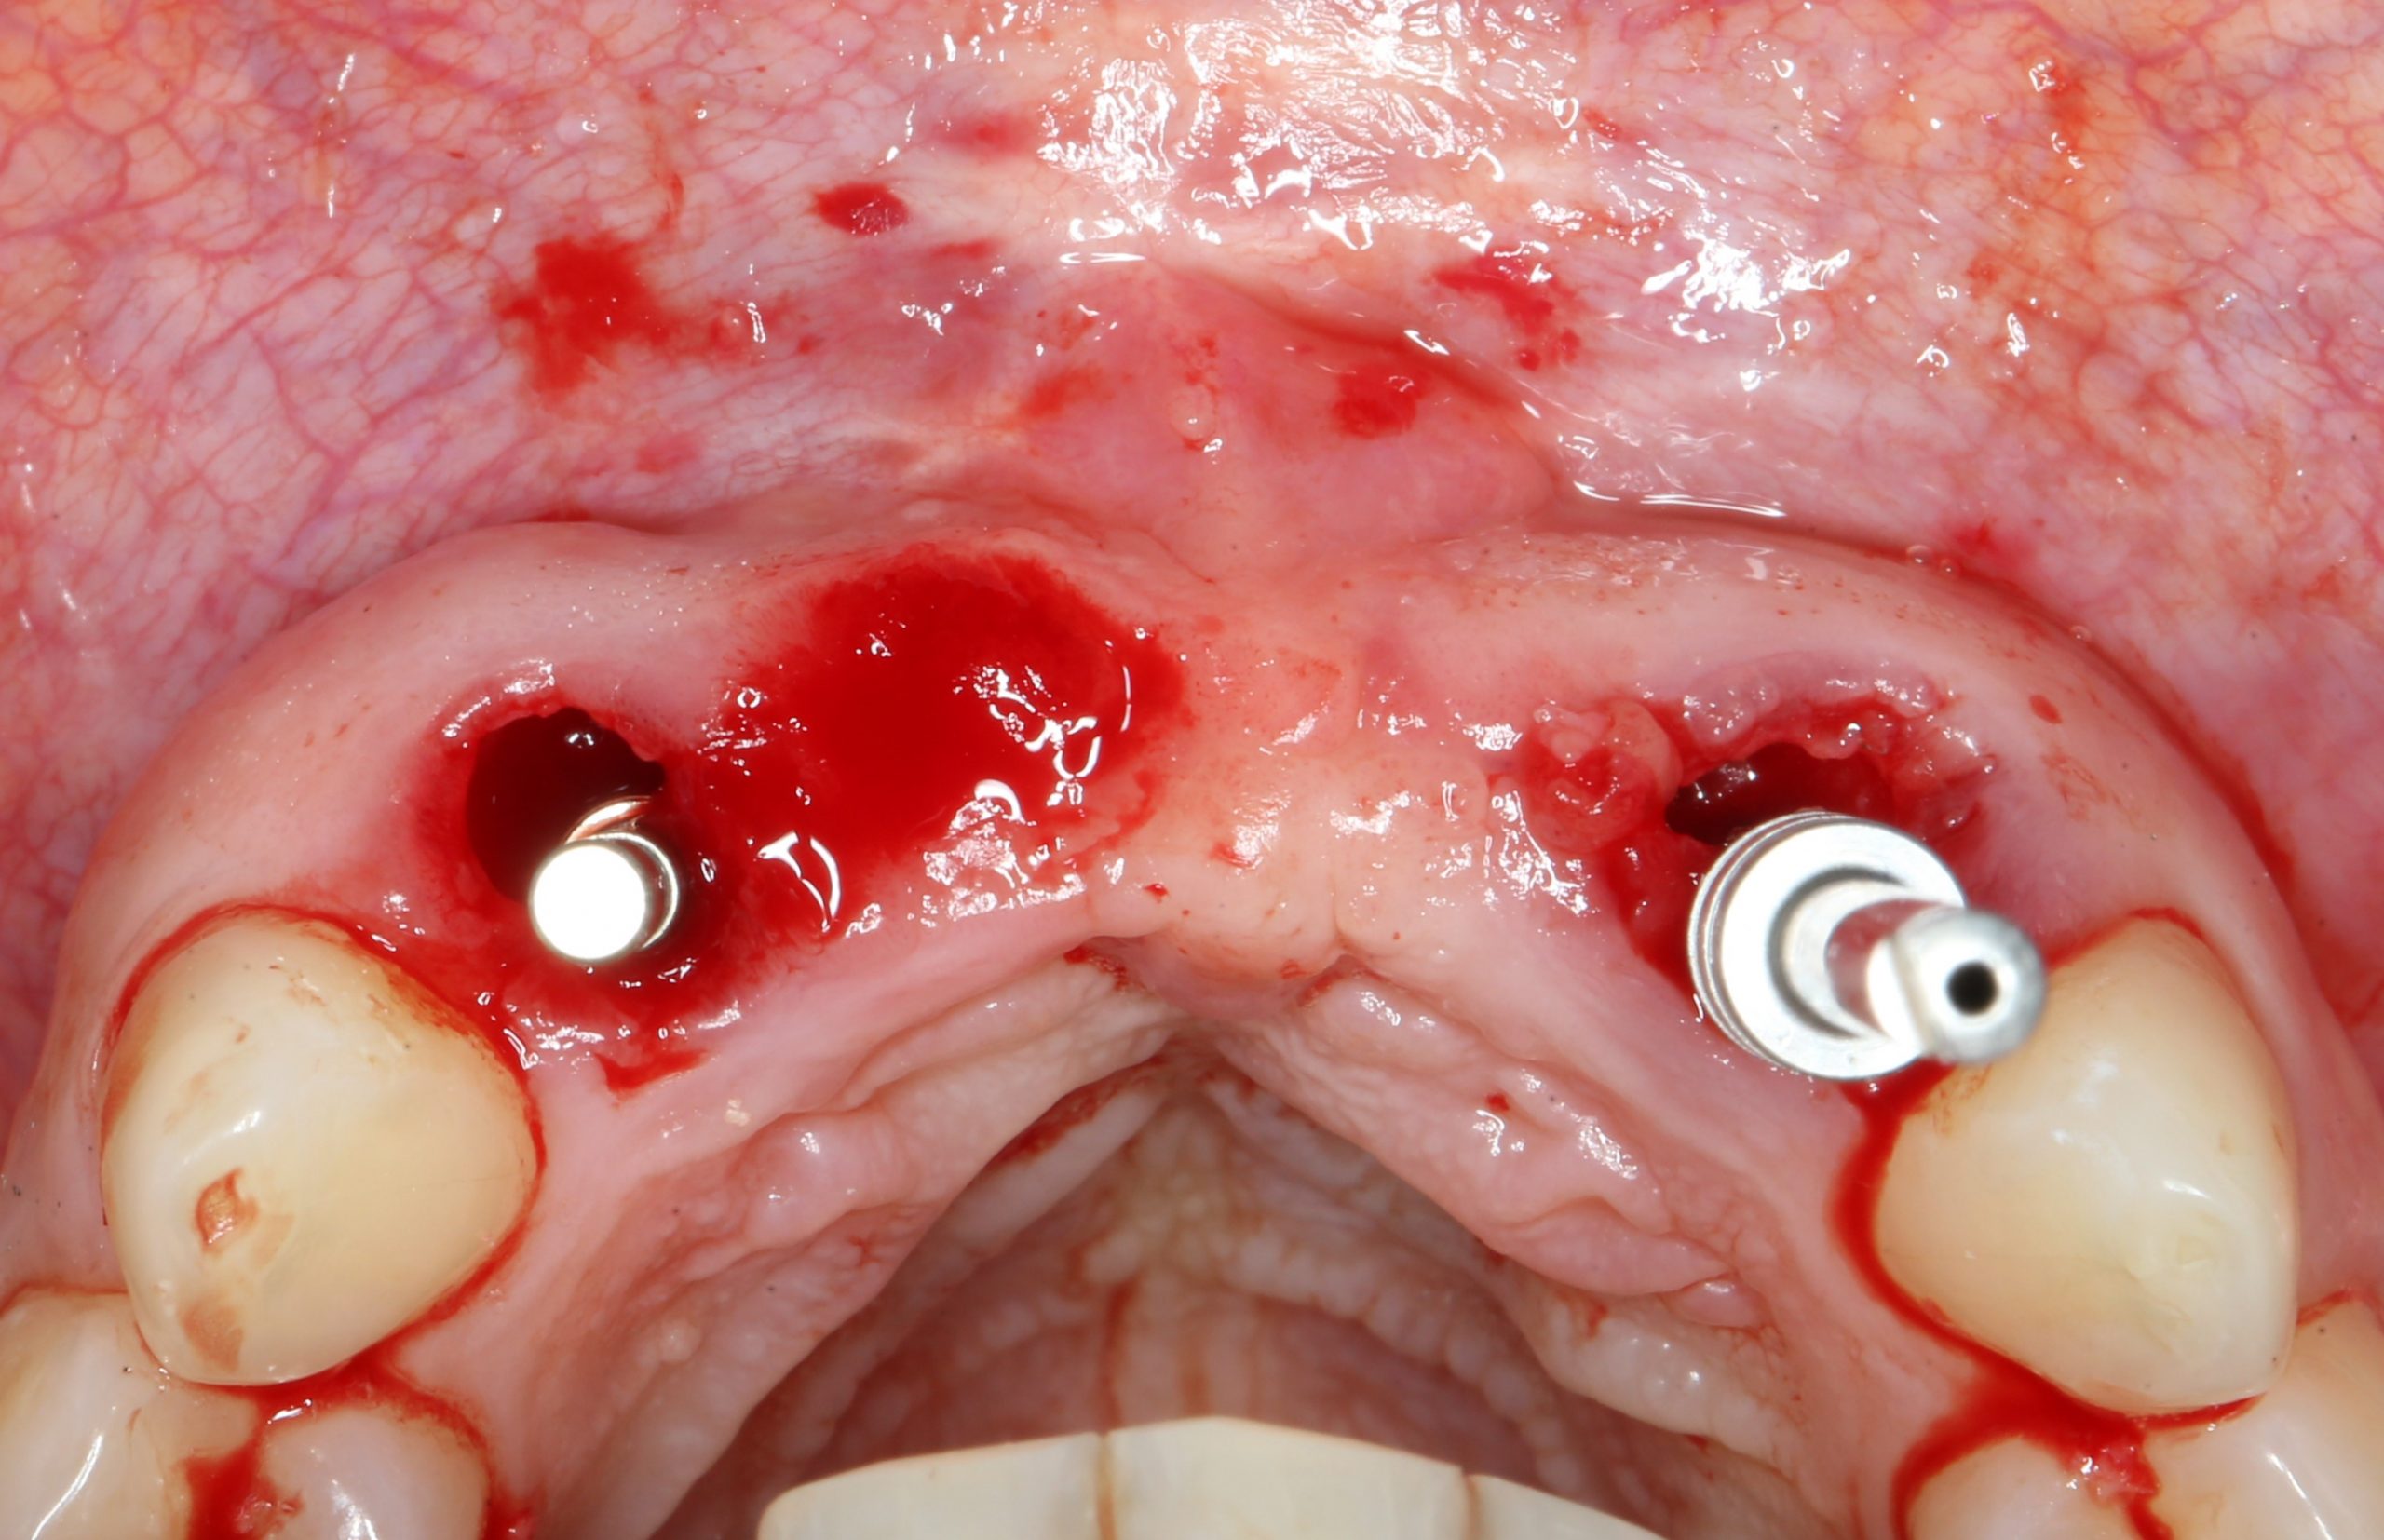

Фиксируем Esthetic Cap на имплантаты. Усилие при установке — 14 Нсм (больше ключ Xive не позволяет):

Еще раз проверим позиционирование имплантатов:

Поскольку трансгингивальная часть временного абатмента Esthetic Cap полностью перекрывает апертуру лунки зуба, мы можем обойтись без швов. Вообще без швов.

Теперь нужно сделать контрольные снимки, чтобы убедиться, что абатменты сели на платформу имплантата. В нашем случае, абатменты пришлось подточить:

Таким образом, мы устанавливаем оба имплантата: